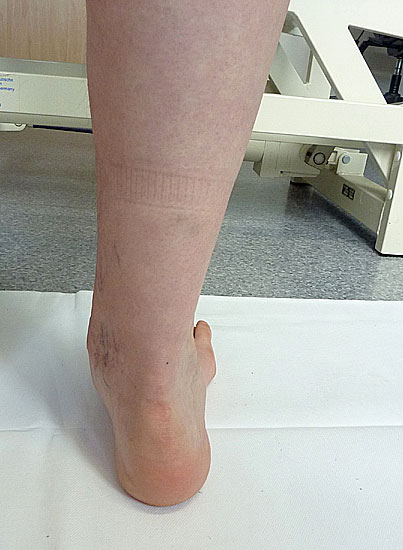

• von hinten

• Morphologie der Beinmuskeln (Seitendifferenz, Waden distal dünn (Abb. 11), Narben)

Inspektion im Liegen von plantar